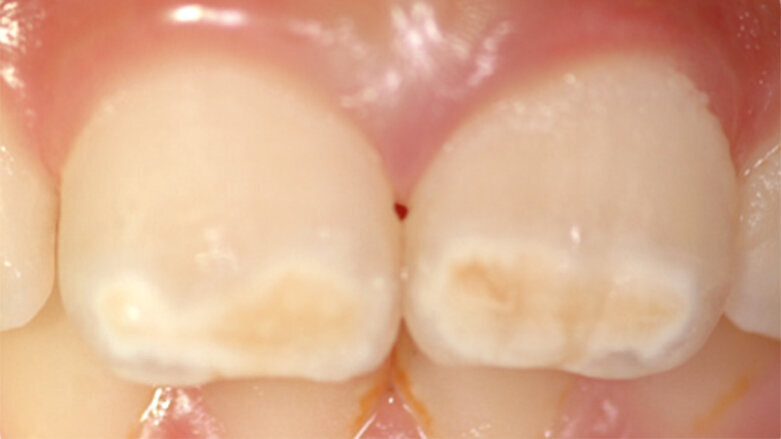

Molárová a incizální hypomineralizace skloviny (Molar Incisor Hypomineralisation – MIH) je globální problém postihující každé sedmé dítě. MIH je běžná vývojová porucha postihující především jeden nebo více prvních stálých molárů. Centrální řezáky mohou být rovněž postiženy, většinou však v menší míře. Může též dojít k hypomineralizaci druhých dočasných molárů (Hypomineralised Lesions on Second Primary Molars – HSPM, hypomineralizační léze druhých stálých molárů) nebo špičáků. U dětí s HSPM je až pětkrát vyšší pravděpodobnost vzniku MIH u stálého chrupu. Závažnost se velmi liší od mírných opacit k posterupčnímu odlomení skloviny.

Klinický vzhled

- Ohraničené opacity v rozpětí od krémově bílé, přes žlutou až po hnědé diskolorace

- Poškozená sklovina má normální tloušťku (dokud nedojde k posterupčnímu odlomení skloviny)

- Léze se mohou vyskytovat asymetricky

- Je-li závažně poškozen první molár, existuje zvýšená pravděpodobnost, že protilehlý molár bude rovněž poškozen

- Léze na centrálních řezácích jsou obvykle mírnější, někdy však mohou být neestetické